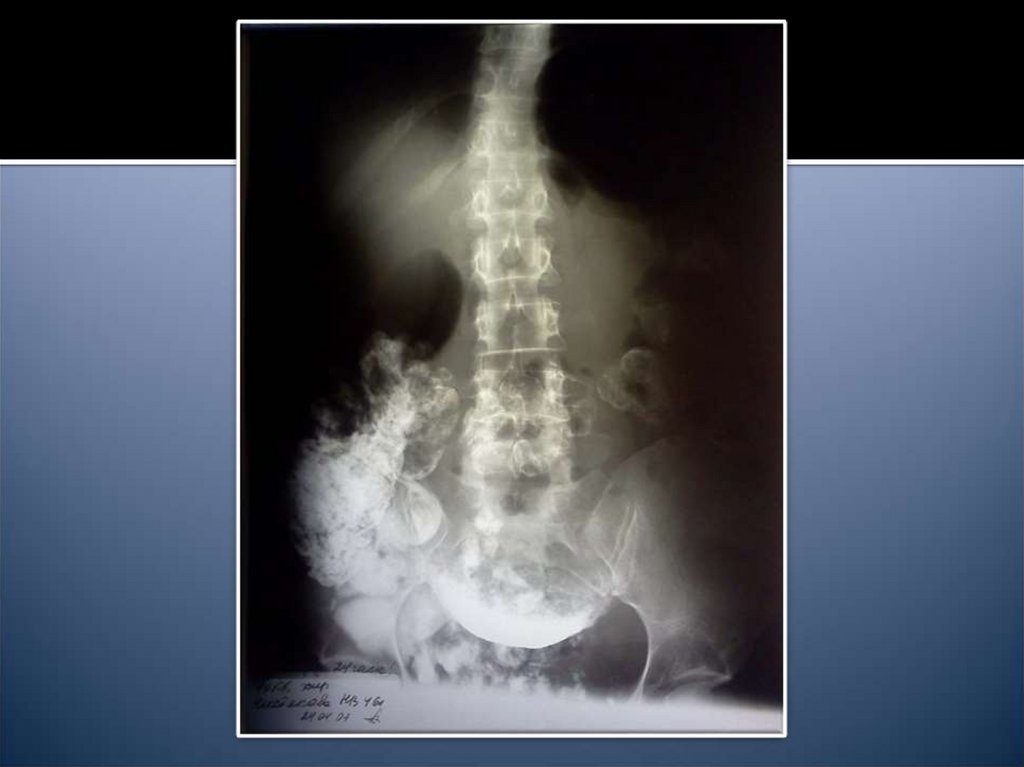

14. Рентгенологические признаки

Чаши Клойбера

Симптом Кивуля (аркады)

Проба Шварца

Пневматоз петель кишечника